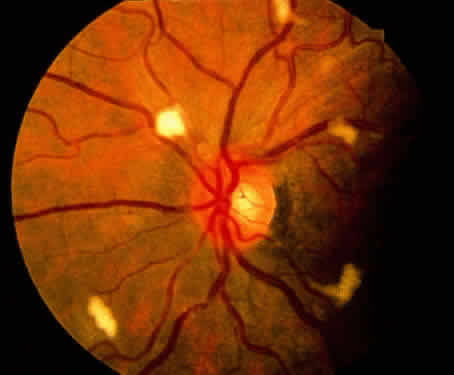

GN, Wilhelmus KR (eds): Ocular Infection and Immunity, Chap 81, pp 1088–1120. St. Louis, Mosby, 1996 190. Dunn JP, Jabs DA: Cytomegalovirus retinitis in AIDS: natural history, diagnosis, and

treatment. AIDS Clin Rev 99, 1995-1996 191. Foster DJ, Dugel PU, Frangieh GT et al: Rapidly progressive outer retinal necrosis in the acquired immunodeficiency

syndrome. Am J Ophthalmol 110:341, 1990 192. Margolis TP, Lowder CY, Holland GN et al: Varicella-zoster virus retinitis in patients with acquired immunodeficiency

syndrome. Am J Ophthalmol 112:119, 1991 193. Engstrom RE Jr, Holland GN, Margolis TP et al: The progressive outer retinal necrosis syndrome: a variant of necrotizing

herpetic retinopathy in patients with AIDS. Ophthalmology 101:1488, 1994 194. Short GA, Margolis TP, Kuppermann DB et al: A PCR based assay for the diagnosis of AIDS associated VZV retinitis. Am J Ophthalmol 123:157, 1997 195. Cunningham ET Jr, Short GA, Irvine AR et al: AIDS-associated herpes simplex virus retinitis: clinical description and

use of a polymerase chain reaction-based assay as a diagnostic tool. Arch Ophthalmol 114:834, 1996 196. Rummelt V, Rummelt C, Gahn G et al: Triple retinal infection with human immunodeficiency virus type 1, cytomegalovirus, and

herpes simplex type 1: light and electron microscopy, immunohistochemistry, and in situ hybridization. Ophthalmology 101:270, 1994 197. Holland GN, Engstrom RE, Glasglow BJ et al: Ocular toxoplasmosis in patients with the acquired immunodeficiency syndrome. Am J Ophthalmol 106:653, 1988 198. Grossniklaus HE, Specht CS, Allaire G, Leavitt JA: Toxoplasma gondii retinochoroiditis and optic neuritis in acquired immune

deficiency syndrome. Ophthalmology 97:1342, 1990 199. Gagliuso DJ, Teich SA, Friedman AH, Orellana J: Ocular toxoplasmosis in AIDS patients. Trans Am Ophthalmol Soc 88:63, 1990 200. Cochereau-Massin I, LeHoang P, Lautier-Frau M et al: Ocular toxoplasmosis in human immunodeficiency virus-infected patients. Am J Ophthalmol 114:130, 1992 201. Berger BB, Egwuagu CE, Freeman WR, Wiley CAA: Miliary toxoplasmic retinitis in acquired immunodeficiency syndrome. Arch Ophthalmol 111:373, 1993 202. Zaidman GW: Neurosyphilis and retrobulbar neuritis in a patient with AIDS. Ann Ophthalmol 18:260, 1986 203. Johns DR, Tierney M, Felsenstein D: Alteration in the natural history of neurosyphilis by concurrent infection